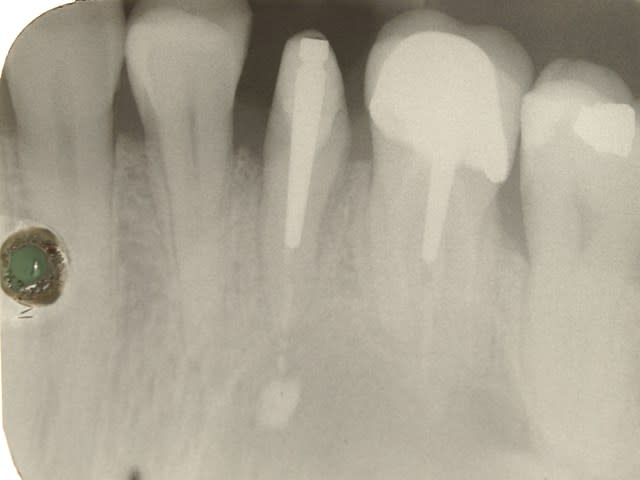

tout frais la radio du 01.07.2014 de la premo extraite et reimplantée le 20.05.2014.

c est le 2 eme cas dont j ai parlé precedemment .

l endo a eté faite avant l extraction .